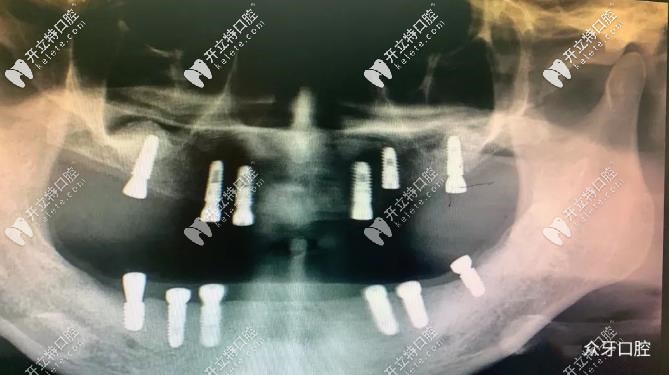

李女士做全口12顆種植牙的CT片

太原眾牙口腔——58歲阿姨,上下頜各種6顆種植體-CT片▲

經(jīng)過(guò)專(zhuān)業(yè)的檢查后,我院盧院長(zhǎng)為李女士制定了種植方案,采用半口種植技術(shù):上下頜各植入6顆種植體;講解了手術(shù)方案后,李女士表示認(rèn)可,手術(shù)順利開(kāi)始。